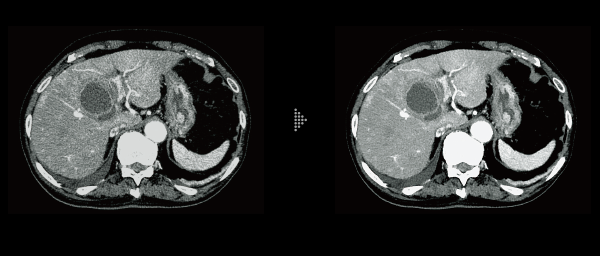

FBP(Left)

Intelli IPV(Right)